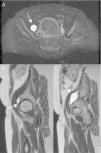

Quiste del labrum acetabular con extensión en la cavidad pélvica

Acetabular labral cyst extending into the pelvic cavity